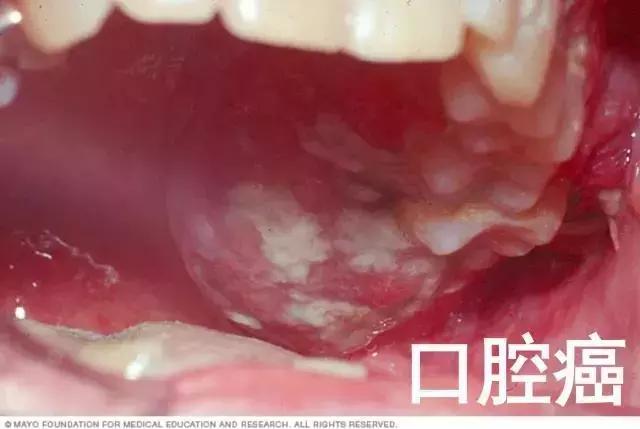

高危型 HPV 感染不止与宫颈癌及癌前病变密切相关,此外还与阴道、肛门、阴唇、阴茎及口咽癌及癌前病变的发生相关。